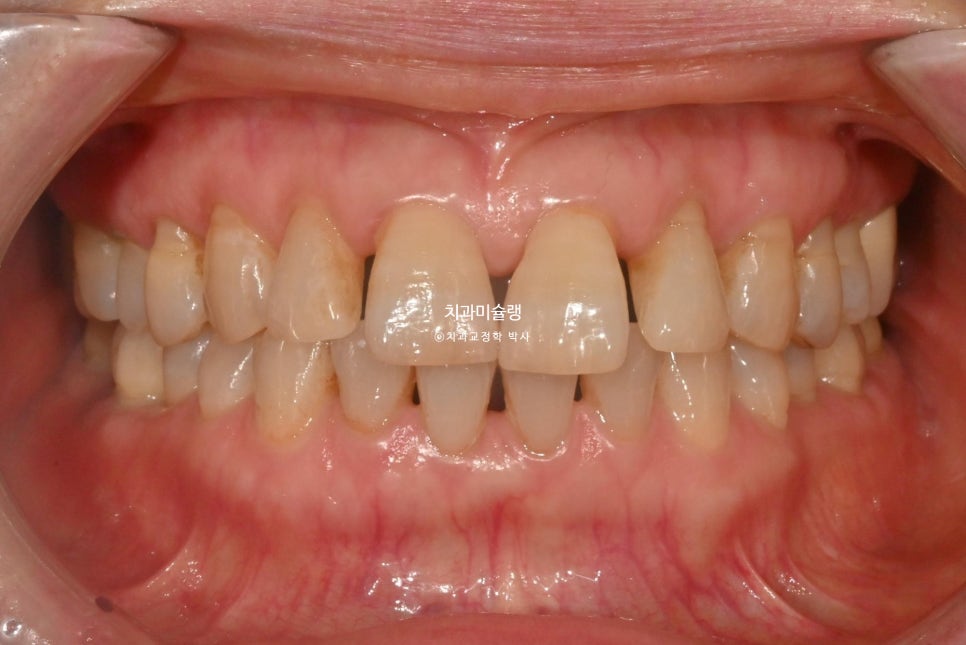

앞니 사이 블랙트라이앵글이 여기저기 보입니다.

측면 사진에서 앞니 사이의 벌어진 큰 틈이 잘 보입니다.

앞니들이 벌어진것 뿐만 아니라 회전된, 소위 “나비치아”입니다.

그에비해 아래앞니는 틈도 없고 틀어짐도 경미하죠.

어금니는 배열이나 교합상 문제가 없습니다.